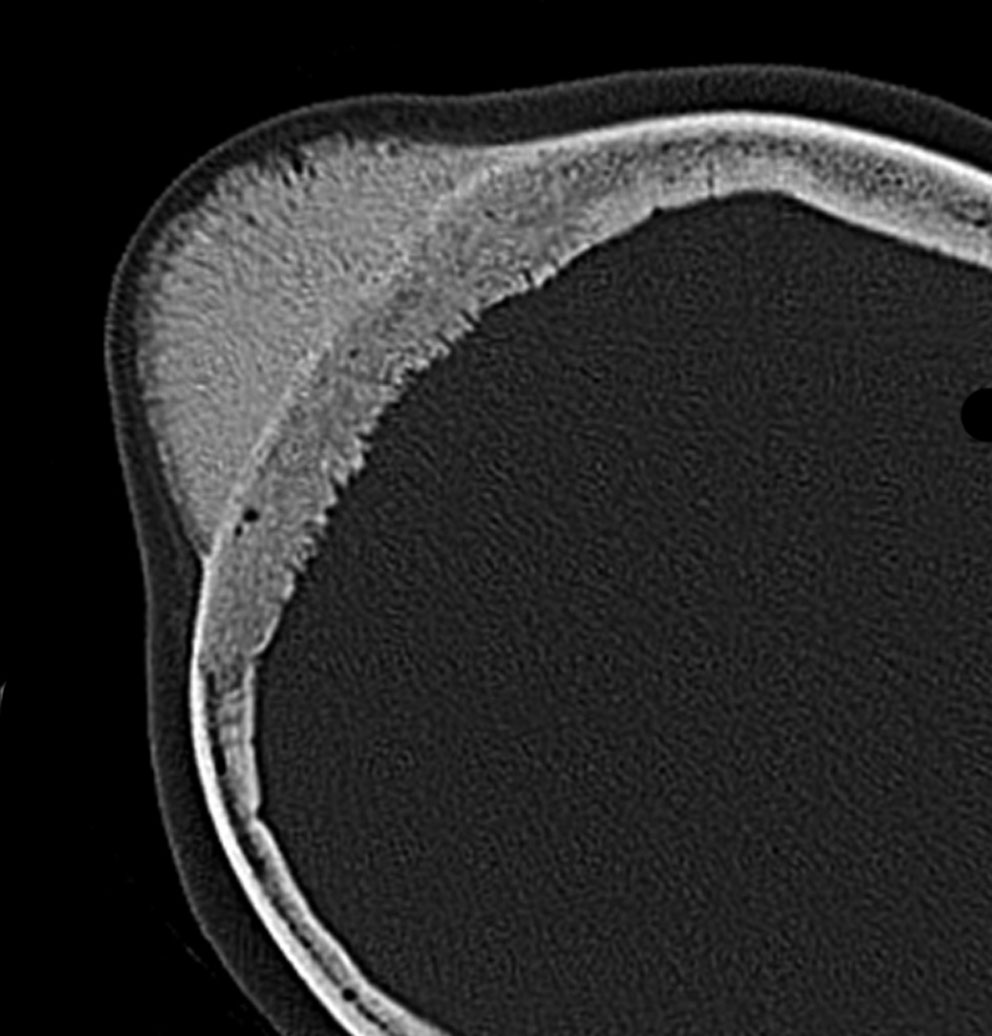

骨内髄膜腫 osseous meningioma

骨内増殖をする髄膜腫です。頭蓋骨腫瘍と間違えるようなものです。触った感じは骨腫ですが,CTでは,表面が毛羽立っていて,頭蓋冠に浸潤していることが特徴です。浅側頭動脈からの豊富な血流があります。

わずかですが頭蓋内にも腫瘍があり,硬膜が肥厚してガドリニウム増強されます。

頭蓋骨をかなり広範におかすので骨は捨てません。開頭して取り外した骨の厚くなっている部分と髄膜腫で軟らかくなっている部分を削除して,それから骨片をオートクレーブで短時間熱処理して,元あった所にもどします。下の画像は手術後1年半が経過したものですが,髄膜腫の再発はなく,熱処理骨弁は吸収されないで生着しています。